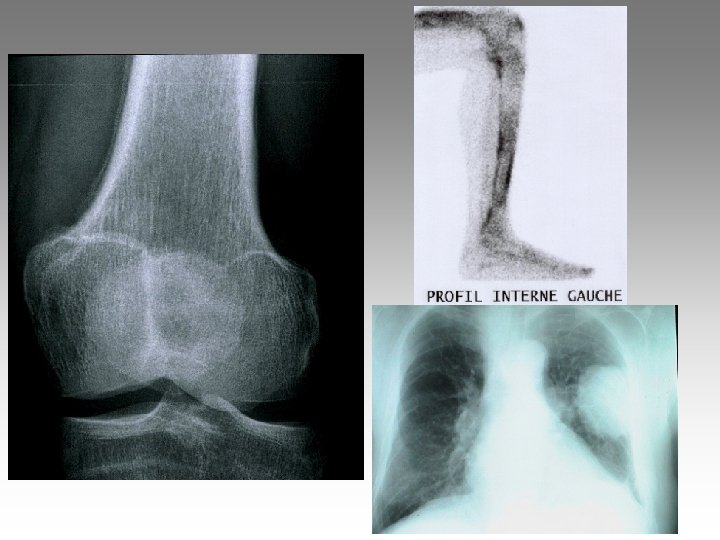

Hanche, T. , fract. fatigue Tendinites bursites, radic. Genou douloureux non traumatique Sémiologie Ponction +++ mécanique inflammatoire Rx inflammation Rx N Rx a. N < 40 ans interligne pincé Arthrose FT - FP contexte +++ > 40 ans Biologie, BS, Rx, IRM, écho interligne normal IRM AND, FF Paget, HOV ONA, OAN OAPH Ostéochond. infection IRM Arthroscopie Scinti. Os. LC Ménisque Coagul. PR, RP, Still, LED, SA…. Goutte, CCA AND ONA Ostéochondrite Pyogène, BK, Gono. , autres Hydarthrose X? Ostéochondromatose Synonite VN, T. , coag.

Genou douloureux non traumatique Sémiologie Ponction +++ mécanique inflammatoire Rx inflammation Rx N Rx a. N < 40 ans interligne pincé Arthrose FT - FP contexte +++ > 40 ans Biologie, BS, Rx, IRM, écho interligne normal IRM AND, FF Paget, HOV ONA, OAN OAPH Ostéochond. infection IRM Arthroscopie Scinti. Os. LC Ménisque Coagul. PR, RP, Still, LED, SA…. Goutte, CCA AND ONA Ostéochondrite Pyogène, BK, Gono. , autres Hydarthrose X? Ostéochondromatose Synonite VN, T. , coag.

Genou douloureux non traumatique Sémiologie Ponction +++ mécanique inflammatoire Rx inflammation Rx N Rx a. N < 40 ans interligne pincé Arthrose FT - FP contexte +++ > 40 ans interligne normal IRM AND, FF Paget, HOV ONA, OAN OAPH infection Biologie, BS, Rx, IRM, écho IRM Arthroscopie Scinti. Os. LC Ménisque Coagul. PR, RP, Still, LED, SA…. Goutte, CCA AND ONA Banal, BK, Gono. , autres Hydarthrose X? Ostéochondromatose Synonite VN, T. osseuse